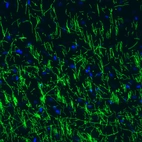

Immunohistochemical staining of human cerebral cortex shows strong immunoreactivity in myelinated fibers.